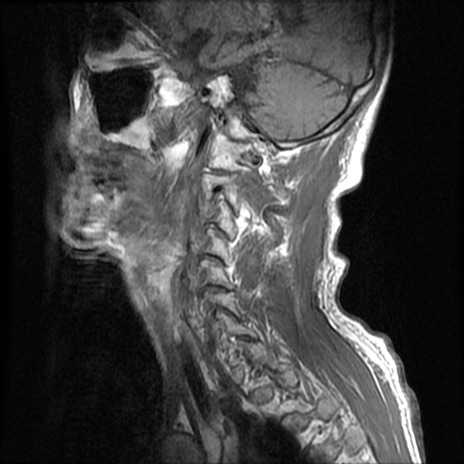

症例46 頚椎MRI T1WI(矢状断像)

【症例】80歳代男性

【主訴】両側頚部〜上肢のしびれ

【現病歴】昨日、自宅内で転倒、その後より上記症状あり。意識障害なし。

【身体所見】両側上肢のallodynia(熱痛覚過敏)あり。MMTおよびDTRは正確な所見取れず。両上肢の挙上はなんとか可能。

異常所見と診断は?

頚椎MRI

T2WI(矢状断像)